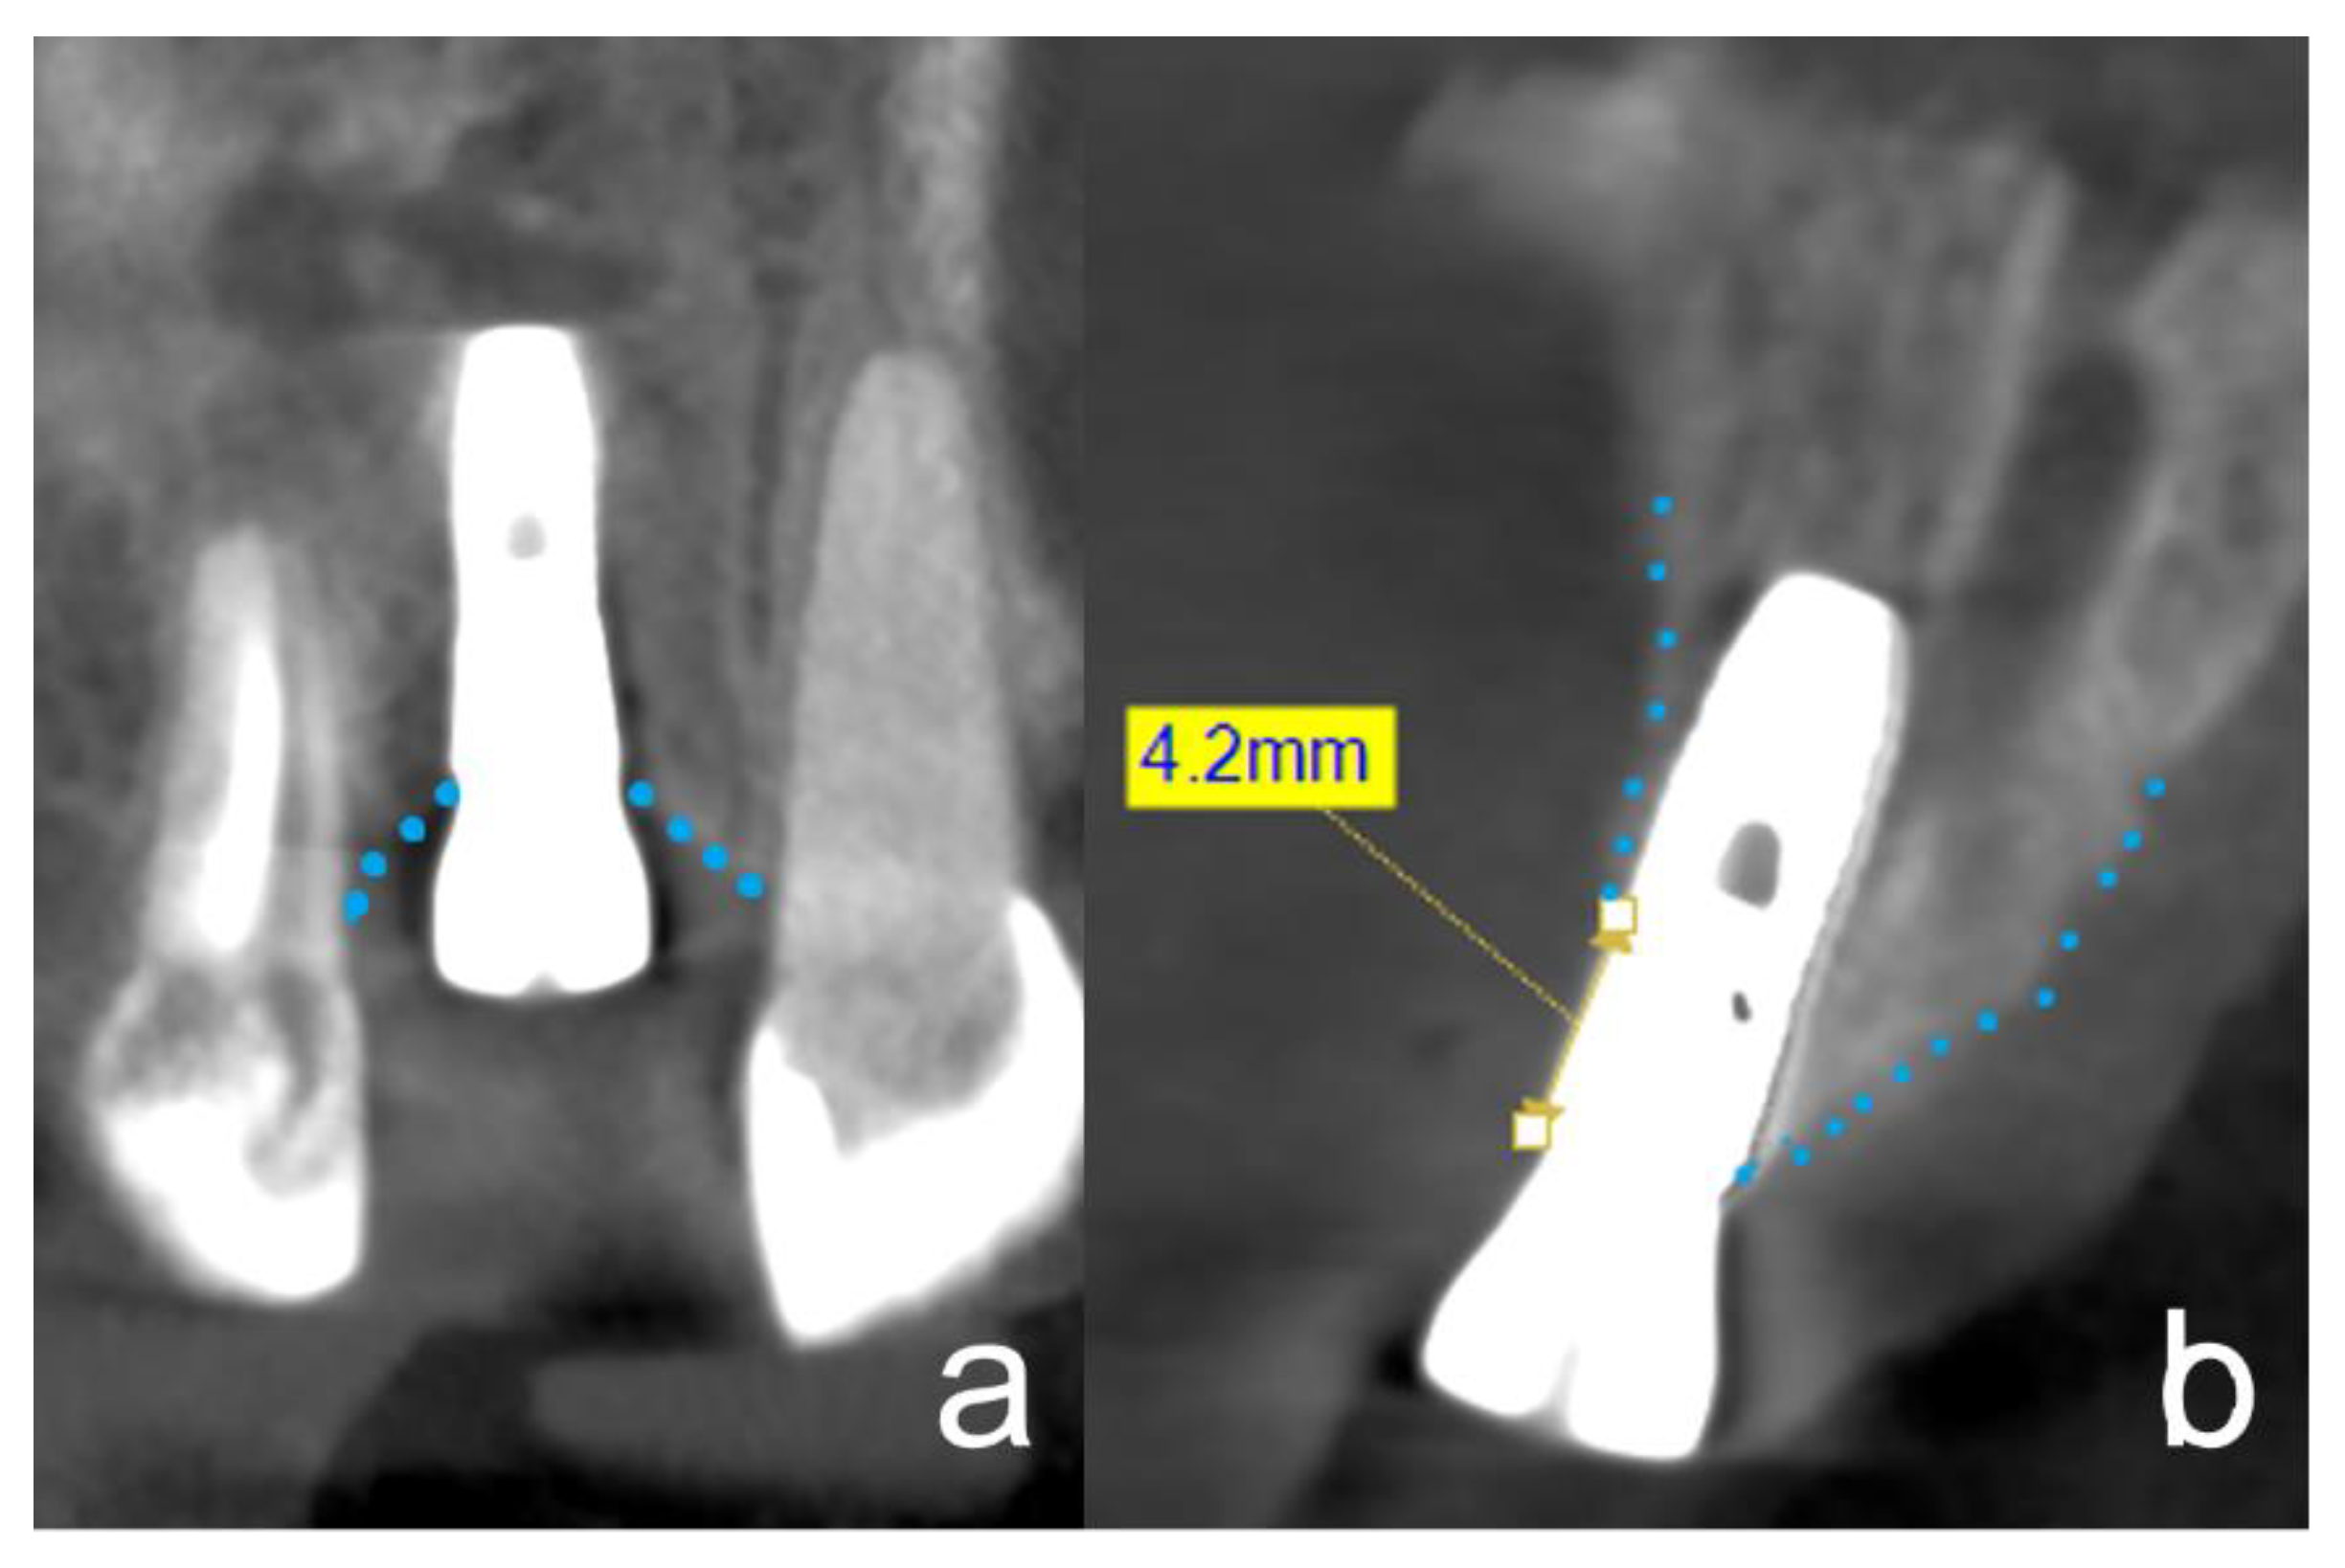

2.6. Radiographic Evaluation of Bone Gain and Resorption